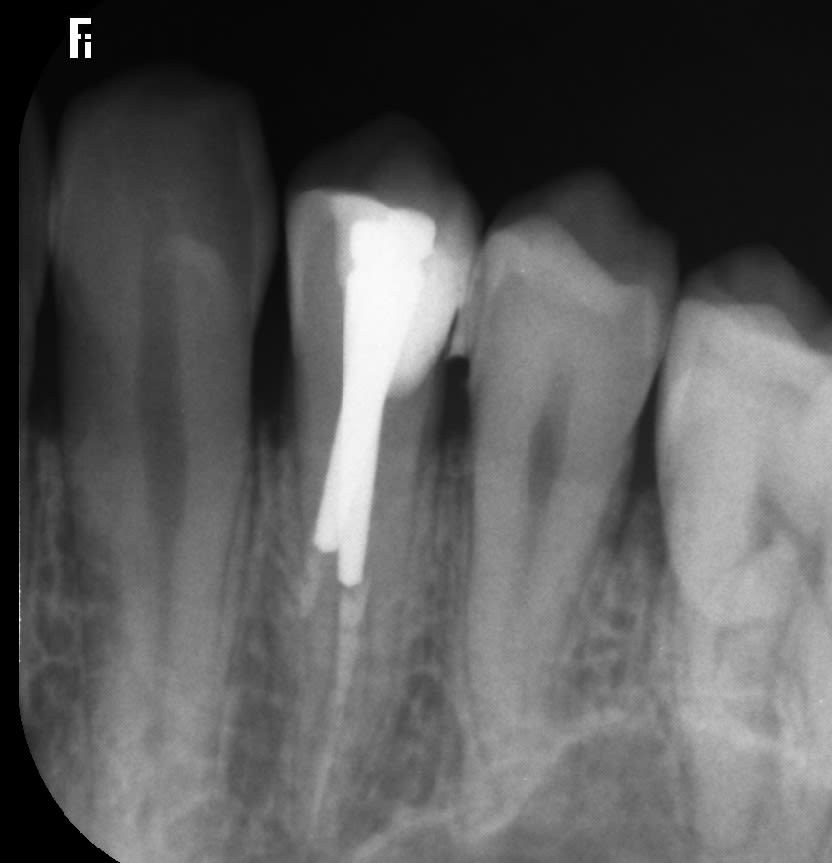

T’as la retro?

Optic’s écrivait:

Gt3pwckvaflauwcwa8rwrw8xeb1i - Eugenol